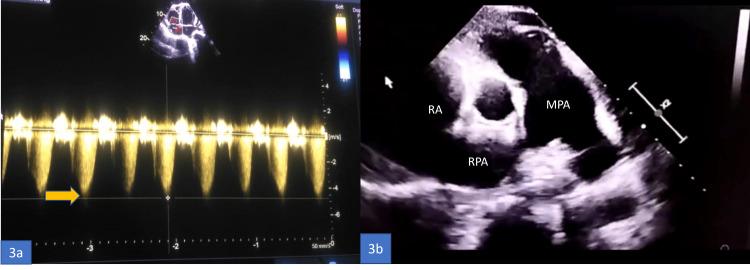

Pulmonary arterial hypertension (PAH) is an uncommon manifestation of systemic lupus erythematosus (SLE), affecting about 0.5% to 23.3% of the population worldwide. The causes of PAH associated with SLE are multifactorial. While it is generally associated with a full-blown picture of SLE, it may rarely be the presenting manifestation of the disease. We describe the case of a middle-aged woman who presented with features of severe PAH due to SLE. She was treated with vasodilators and immunosuppression (steroids and mycophenolate mofetil), with a partial response to treatment at six months follow-up.

肺动脉高压(PAH)是系统性红斑狼疮(SLE)的一种罕见表现,在全球约0.5%至23.3%的人群中出现。与SLE相关的PAH病因是多因素的。虽然它通常与典型的SLE症状相关,但也可能极少作为该疾病的首发表现。我们描述了一名中年女性的病例,她因SLE出现了严重PAH的症状。她接受了血管扩张剂和免疫抑制治疗(类固醇和霉酚酸酯),在六个月的随访中治疗有部分反应。